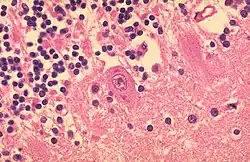

V minulosti se dělaly také histologické řezy, u nemocných se často vyskytovaly typické intracytoplasmatické inkluze (tvořené virovými proteiny) zvané Babes-Negriho tělíska. Nejčastěji se tvoří v Purkyňových a pyramidálních buňkách Amonova rohu. Přestože jsou patognomickým znakem pro vzteklinu, od použití histologie se v diagnostice vztekliny upustilo, jejich nepřítomnost totiž vzteklinu ani zdaleka nevylučuje.[71][74]